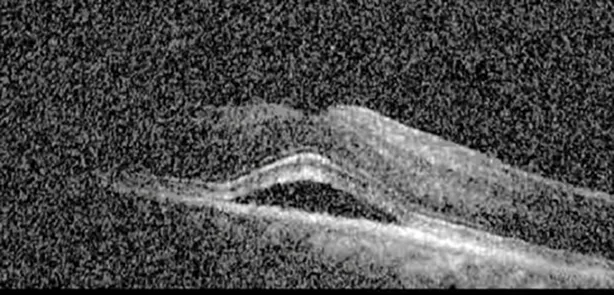

The patient began treatment with oral pemigatinib daily and was followed up for an ophthalmic examination during the second treatment cycle approximately 5 weeks into the treatment process. The patient had at this stage received 28 doses of 13.5 mg per day, which was administered in cycles of 14 on-days and 7 off-days, and had no visual or ophthalmic complaints. The non-corrected VA was OD 20/30 + 1 and OS 20/20. The OCT examinations revealed subfoveal SRF bilaterally. The fundus examination was otherwise unremarkable outside the patient’s prior documented peripheral drusen. Repeat autofluorescence was overall unchanged, though a slight hypofluorescent ring may be visualized in Figure 2. The current pemigatinib protocol recommendation for asymptomatic patients suggests no dose modification; however, with worsening presentation or positive symptoms, it is recommended to withhold pemigatinib. After discussion with the patient’s oncologist, it was decided to continue the medication at this time. Serial monitoring of the patient’s symptoms, vision, and SRF were conducted on specific days during active treatment cycles and days off-cycle to monitor the SRF. Subsequent evaluations demonstrated complete resolution of SRF while off-cycle, and asymptomatic re-accumulation of fluid while on-cycle with varying levels of VA. (Table 1) As we see demonstrated in the table below, in the later stages of the active cycles, such as day 13 of 14 of cycle 2, day 13 of 14 of cycle 3, day 13 of 14 of cycle 4, and day 14 of 14 on cycle 5, the patient’s VA showed no correlative changes based on the presence of SRF. The fluctuations in the patient’s VA certainly occurred, but were likely to be secondary to surface changes, as certain off-cycle days actually presented with lower acuities than days when the SRF was present on OCT examination.

Table 1

| Cycle, day, on/off | VA OD; OS | CMT OD; OS | OCT OD | OCT OS |

| Cycle 3, day 6/14, on | 20/40−1; 20/30−1 | 306; 301 | ![]() | ![]() |

Highlights the visual acuity, central macular thickness, and the physical OCT of the macula for this patient in both the right and left eyes during various stages of the patient's chemotherapy treatment cycle.